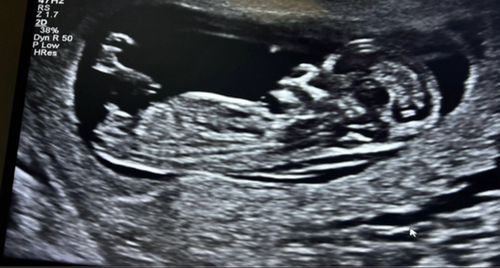

Iemand een idee? 12+3 😄

Hier nog een foto! 😊